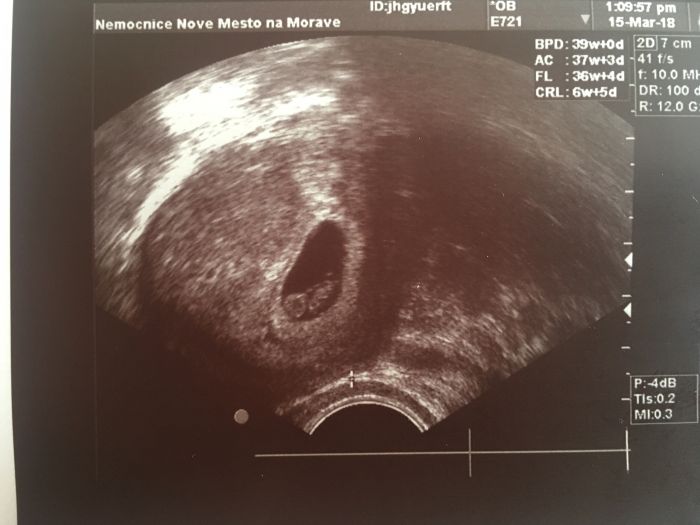

My dnes koncime 12tt..zitra 12+1..tp mame 24.10...ale pocitam ze bude listopadek..nu a na utz.vychazelo o 2dny mene..

Utz..ze 7tt..kvuli tomu zda bije srdicko..ted jdeme 12teho..uz se s tatkou tesime...dnesni krece nas oba vydesili..uz nejsem nejmladsi..?